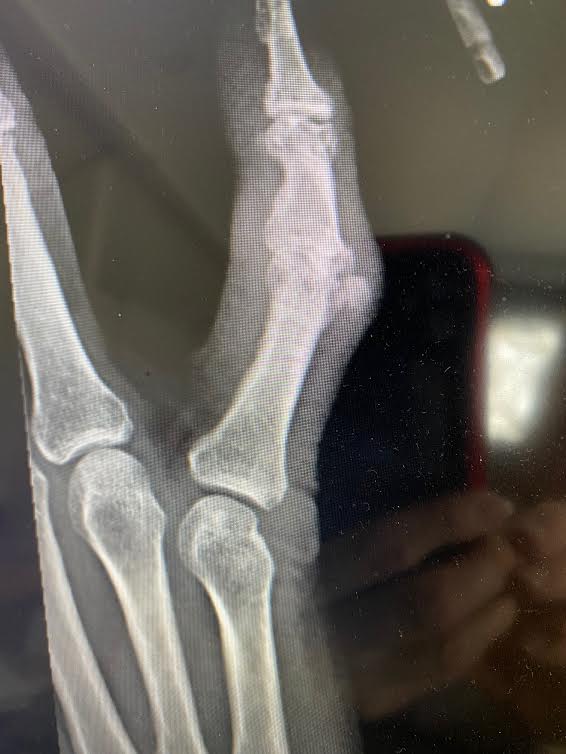

I broke the knuckle straight across and knocked a chip out of it.

This time I knocked the little joint out of place

Arthritis has taken over the first knuckle and will take over the tiny knuckle at the tip.